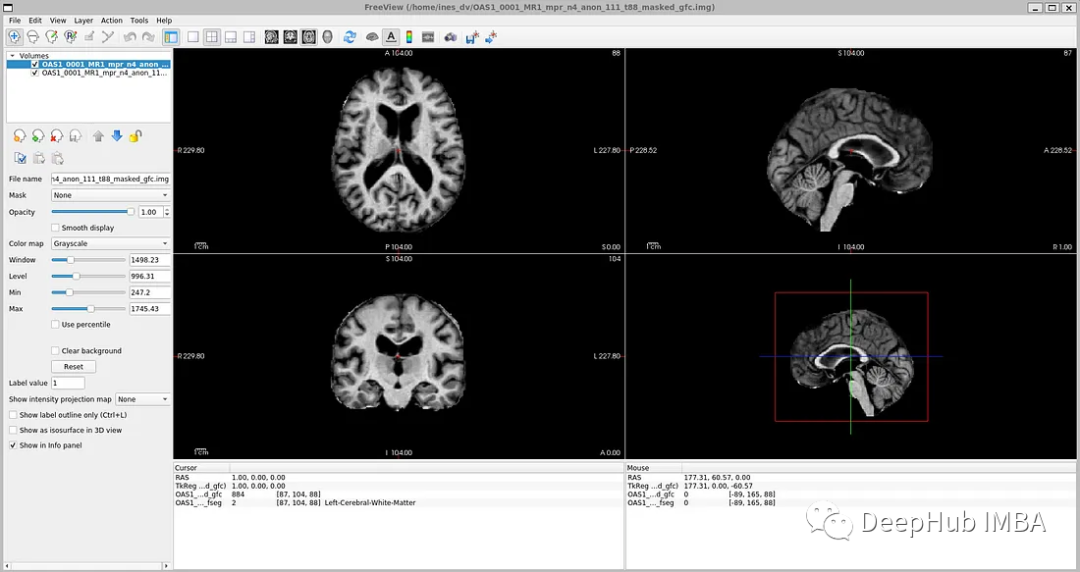

如果你打开' oasis_crosssectional_disc1 .tar.gz ',你会发现每个主题都有不同的文件夹。例如,对于主题OAS1_0001_MR1,是这样的:

镜像数据文件路径:disc1\OAS1_0001_MR1\PROCESSED\MPRAGE\T88_111\ oas1_0001_mr1_mpr_n4_anon_111_t88_masked_ggc .img

标签文件:disc1\OAS1_0001_MR1\FSL_SEG\OAS1_0001_MR1_mpr_n4_anon_111_t88_masked_gfc_fseg.img

为了可视化带有相应标签的图像,可以使用TorchIO,这是一个Python库,用于深度学习中多维医学图像的加载、预处理、增强和采样。

image\_filename \= root\_dir + '/Oasis\_Data\_Processed/OAS1\_0001\_MR1\_mpr\_n4\_anon\_111\_t88\_masked\_gfc.nii'

label\_filename \= root\_dir + '/Oasis\_Labels\_Processed/OAS1\_0001\_MR1\_mpr\_n4\_anon\_111\_t88\_masked\_gfc\_fseg.nii'

subject \= torchio.Subject\(image\=torchio.ScalarImage\(image\_filename\), label\=torchio.LabelMap\(label\_filename\)\)

subject.plot\(\)